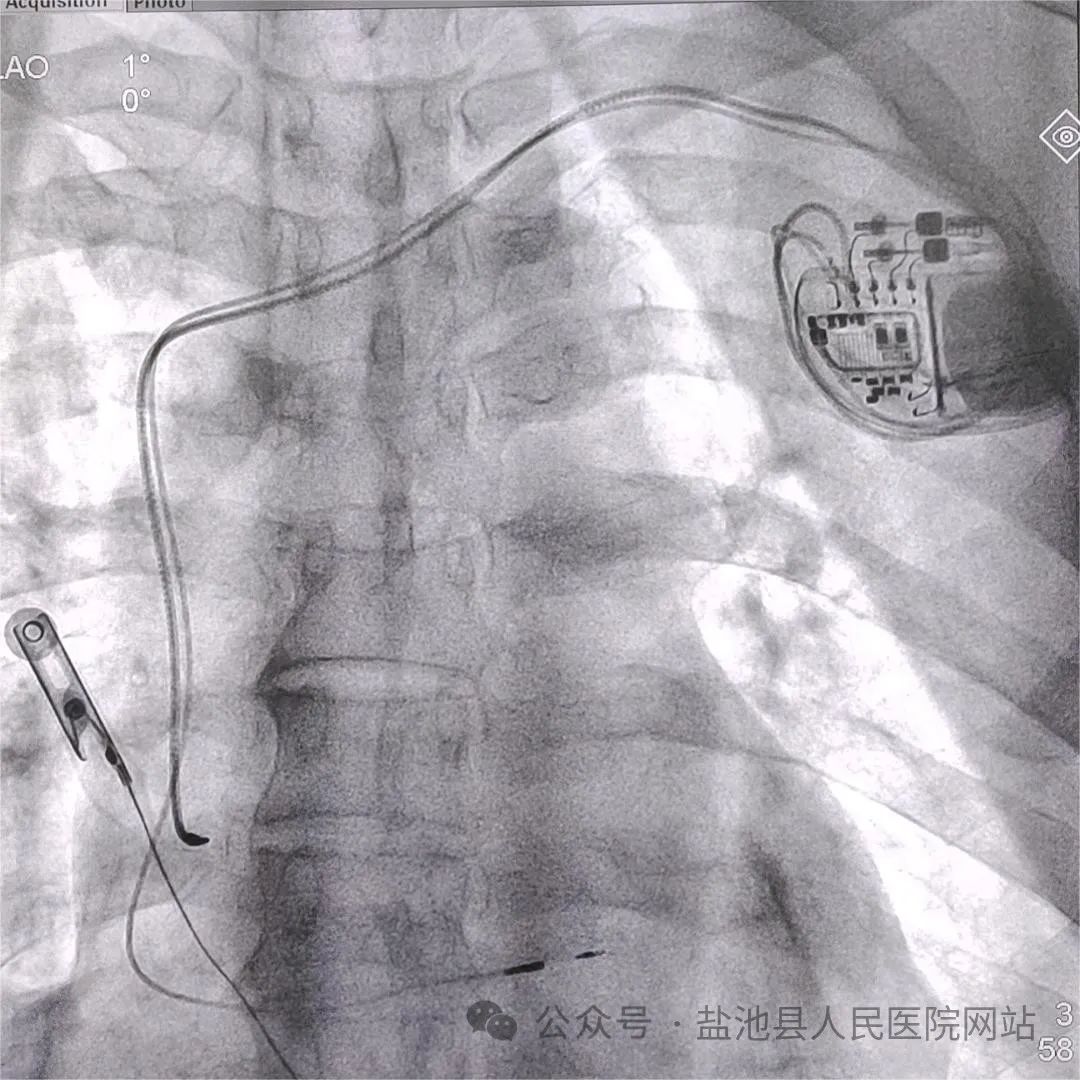

团队成员精心准备,精诚合作,精细操作,精准定位,通过左锁骨下静脉穿刺,在X线及多导电生理仪指导下精确找到患者的左束支起搏区域,并将电极从右心室间隔侧精准旋入到左心室内膜下的左束支区域,从而使电刺激信号通过该路径向下传导,手术过程顺利,左束支电位明显,起搏各参数满意,电极固定牢固,手术取得圆满成功。